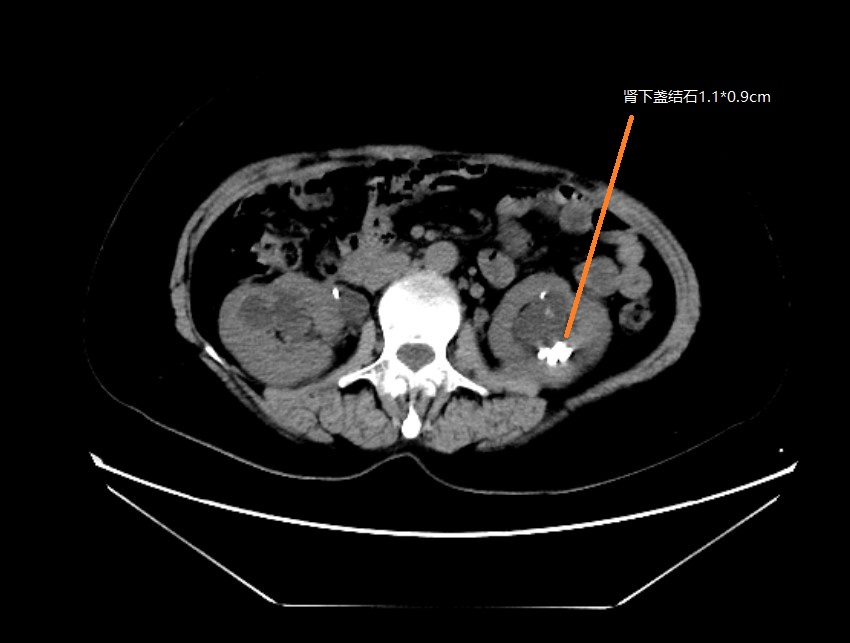

患者中年女性,約1年前曾因雙側(cè)腎結(jié)石,右輸尿管結(jié)石行體外碎石治療,治療后未復(fù)查,去年年底查體發(fā)現(xiàn)雙腎結(jié)石及右側(cè)輸尿管結(jié)石,因右輸尿管扭曲梗阻嚴(yán)重于我院行腹腔鏡下右側(cè)輸尿管切開取石術(shù),本次為處理左側(cè)腎結(jié)石第2次入院,入院后復(fù)查CT如下:

入院后患者存在尿路感染,按照診療指南給予抗生素治療1周,復(fù)查感染控制良好。經(jīng)多學(xué)科會(huì)診討論病情,認(rèn)為患者腎盂結(jié)石直徑大于2cm,積水明顯,腎下盞同時(shí)存在結(jié)石1*0.9cm,結(jié)石負(fù)荷量較大。首選經(jīng)皮腎鏡激光碎石取石術(shù),替代方案為:1。腹腔鏡腎盂切開取石術(shù),2。輸尿管軟鏡下激光碎石取石術(shù)?;颊呒凹覍倏紤]后同意行經(jīng)皮腎鏡激光碎石取石術(shù)。泌尿外科醫(yī)護(hù)團(tuán)隊(duì)積極完善術(shù)前準(zhǔn)備,排除手術(shù)禁忌后,在手術(shù)室麻醉護(hù)理及B超室等兄弟科室的輔助下成功行微通道經(jīng)皮腎鏡激光碎石取石術(shù)。